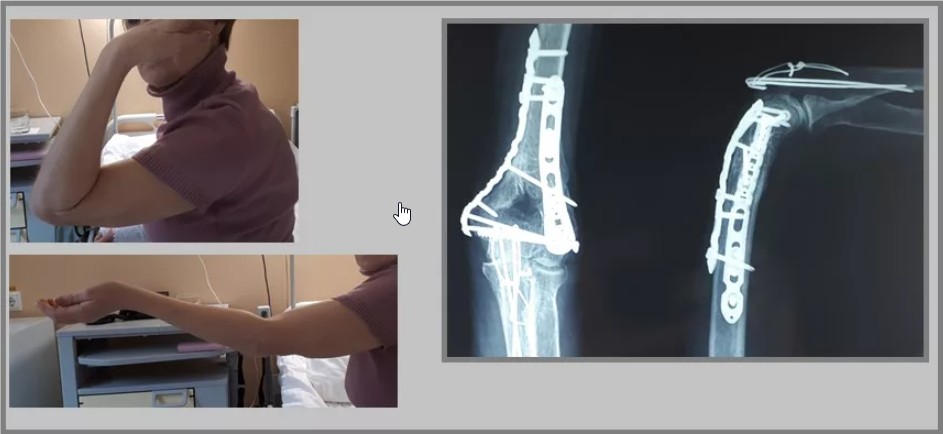

При появлении таких симптомов следует незамедлительно обращаться за профессиональной помощью к опытным специалистам. Доктор проведёт комплексное обследование и поставит точный диагноз. Для этого проводятся такие исследования, как рентегнография, МРТ и мультиспиральная компьютерная томография. В соответствии с полученными результатами будет составлен оптимальный план лечения с последующей реабилитацией для полноценного выздоровления. Качественное восстановление выполняется специалистами нашего современного центра реабилитации «Исток» во Владикавказе.

Эффективное восстановление после перелома мыщелка проводится по недорогой стоимости командой квалифицированных и профессиональных специалистов современного реабилитационного центра «Исток» во Владикавказе. И для каждого больного у нас применяется персональный подход, позволяющий учитывать все особенности ситуации для достижения максимально продуктивного результата в каждом конкретном случае. Проводится оно сразу после осуществления консервативного или хирургического лечения.